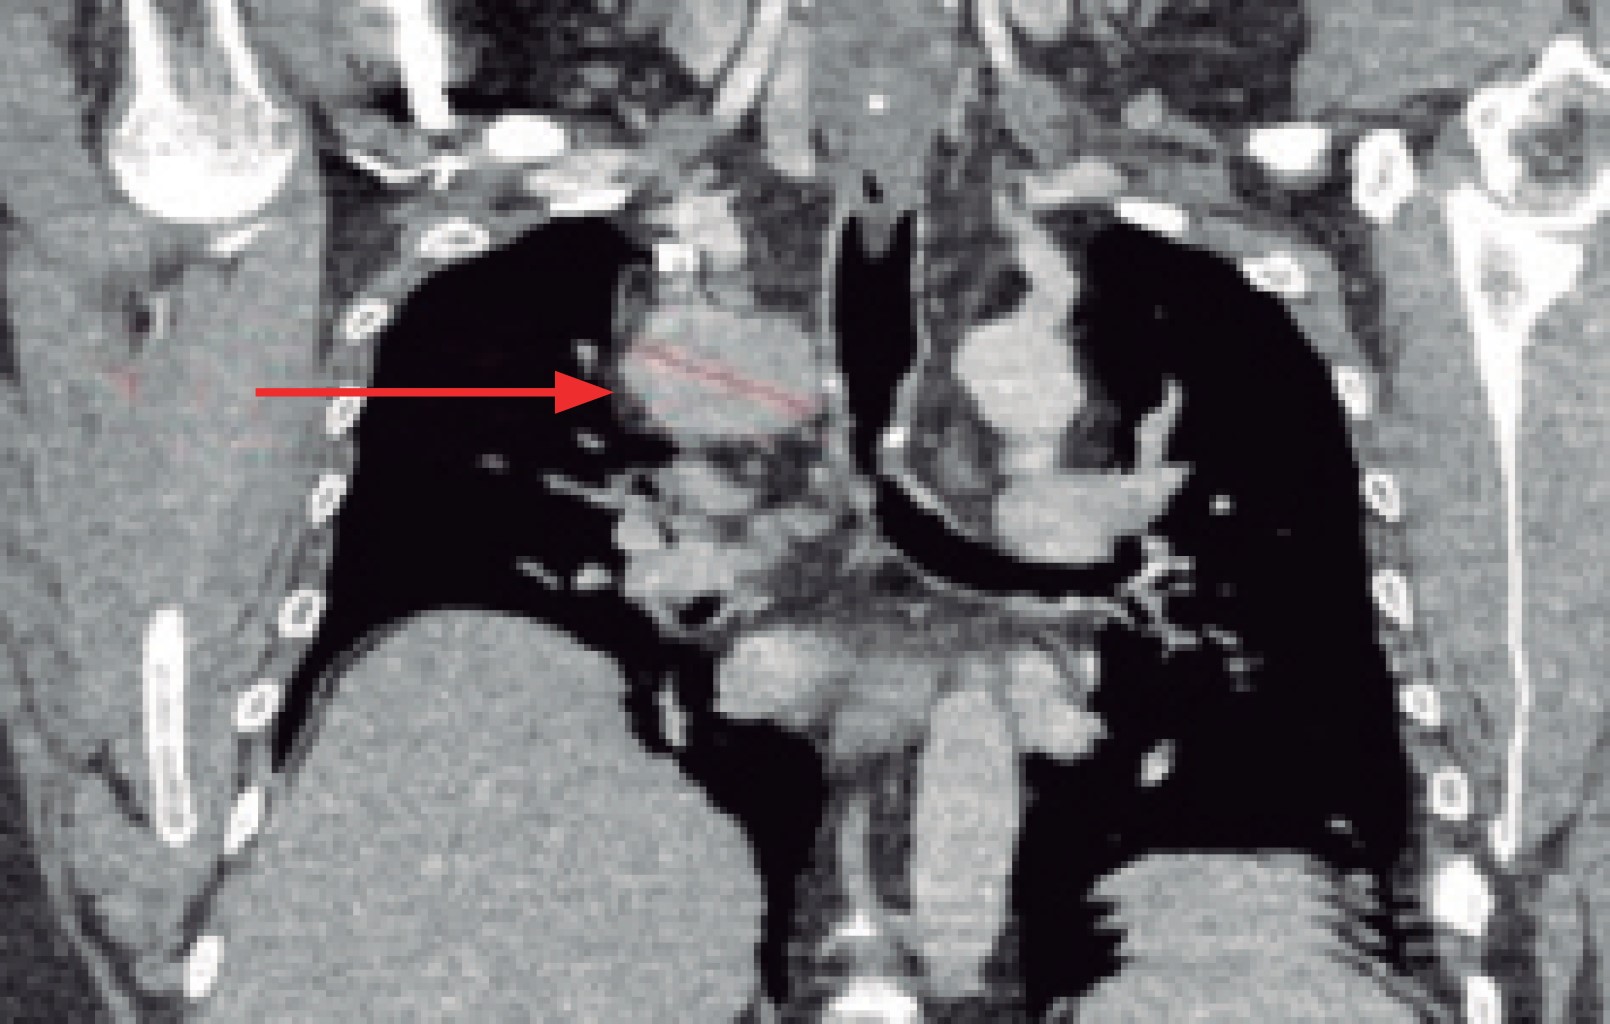

This is a 47-year-old man who had been managed for 15 years for gout, so he went to rheumatology consultation, where he refers respiratory symptoms of three months of evolution characterized by dry cough in accesses, in addition to facial edema and upper extremities. In his last consultation he requested a routine chest X-ray where a mediastinal widening was observed, so a computed tomography scan was performed, which showed a mass in the middle mediastinum of approximately 7 × 5 centimeters in diameter, with extrinsic compression of the superior vena cava and azygos vein, elevation of the homolateral hemidiaphragm, in addition to severe hepatomegaly (Figure 1).

Figure 1